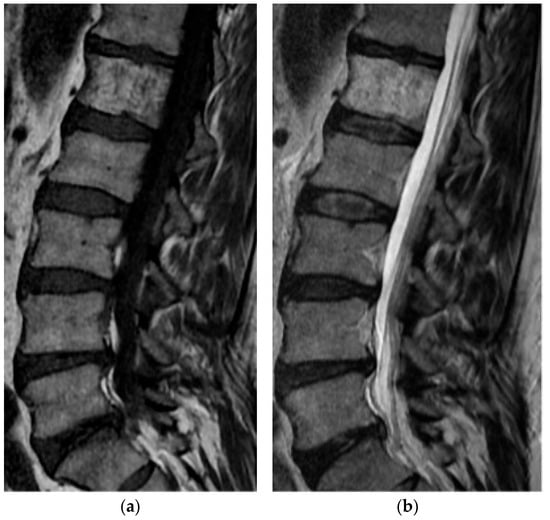

2.5.2. Aneurysmal Bone Cyst